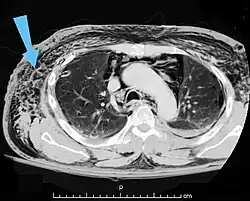

Les cas importants d'emphysème sous-cutané sont faciles à diagnostiquer en raison des signes caractéristiques de l'affection. Dans certains cas, les signes sont subtils, ce qui rend le diagnostic plus difficile. L'imagerie médicale est utilisée pour diagnostiquer la maladie ou confirmer un diagnostic établi à l'aide de signes cliniques. Sur une radiographie du thorax, l'emphysème sous-cutané peut être vu comme des stries radiotransparentes dans le modèle attendu du groupe de muscles principaux du pectoral. L'air présent dans les tissus sous-cutanés peut interférer avec la radiographie du thorax, ce qui peut masquer des affections graves comme le pneumothorax. Elle peut également réduire l'efficacité de l'échographie thoracique. D'autre part, comme l'emphysème sous-cutané peut être visible sur les radiographies du thorax avant un pneumothorax, sa présence peut être utilisée pour déduire celle de cette dernière lésion. L'emphysème sous-cutané peut également être observé sur les scanners, les poches d'air apparaissant comme des zones sombres. Le scanner est si sensible qu'il permet généralement de trouver l'endroit exact d'où l'air pénètre dans les tissus mous. En 1994, M. T. Macklin et C. C. Macklin ont publié d'autres aperçus sur la physiopathologie du syndrome de Macklin spontané survenant à la suite d'une grave crise d'asthme. La présence d'un emphysème sous-cutané chez une personne qui semble très malade et fébrile après une crise de vomissements suivie d'une douleur thoracique gauche est très évocatrice du diagnostic du syndrome de Boerhaave, qui est une urgence vitale causée par une rupture de l'œsophage distal. L'emphysème sous-cutané peut être une complication de l'insufflation de CO2 avec la chirurgie laparoscopique. Une augmentation soudaine du CO2 en fin de marée après la hausse initiale qui se produit avec l'insufflation (les 15-30 premières minutes) devrait faire suspecter un emphysème sous-cutané. Il est à noter que l'oxymétrie de pouls et la pression des voies aériennes ne varient pas dans l'emphysème sous-cutané, contrairement à l'intubation endobronchique, au capnothorax, au pneumothorax ou à l'embolie au CO2.